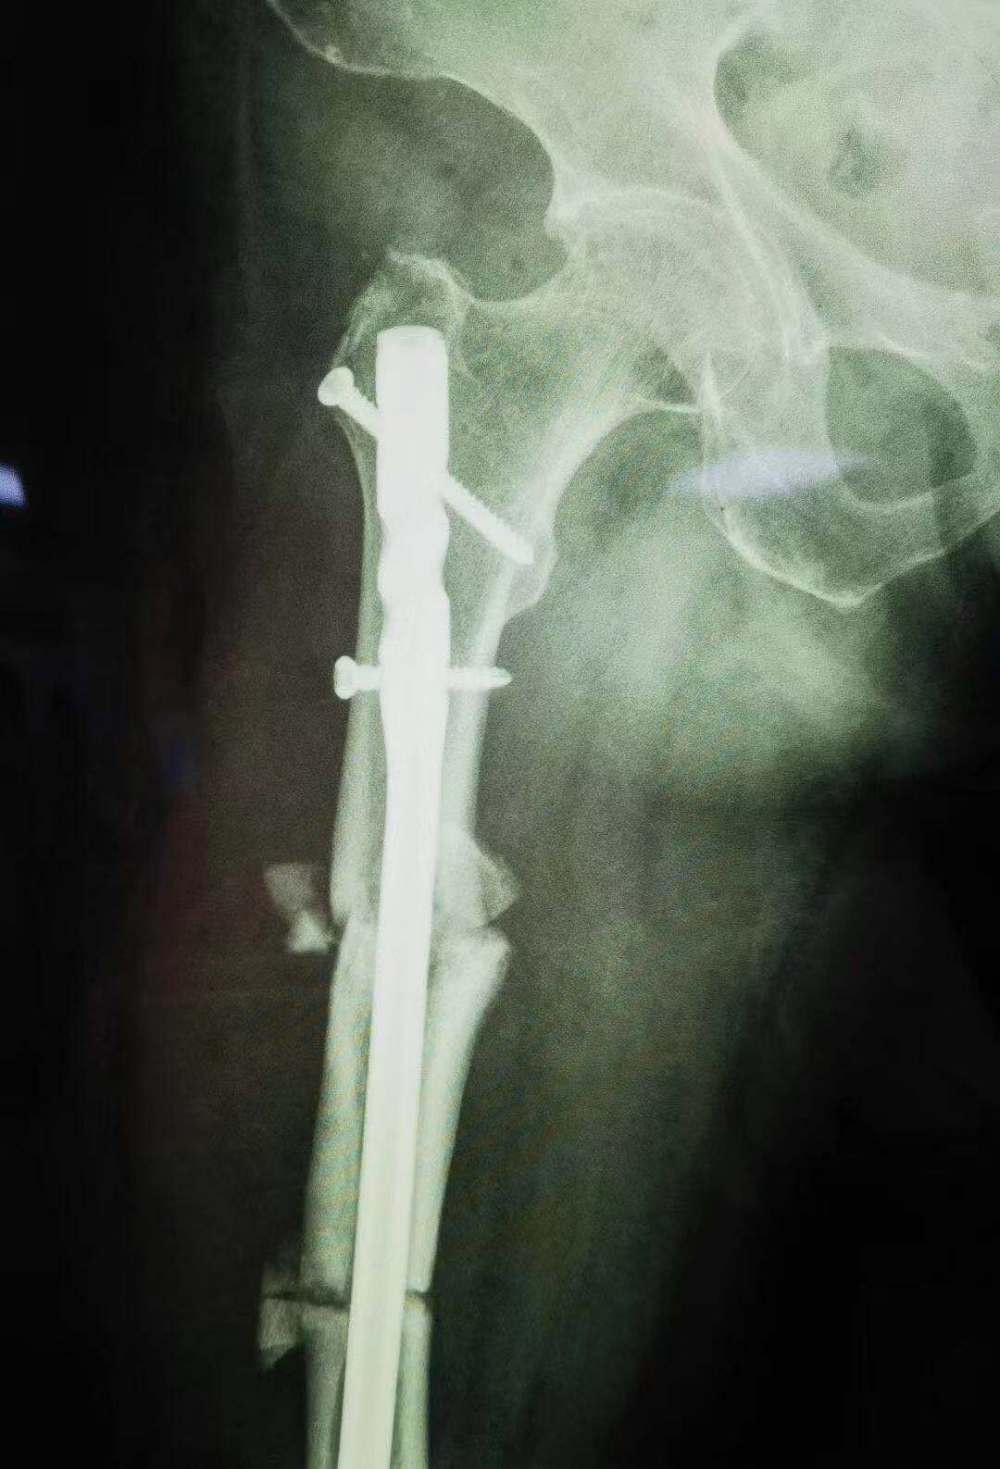

據(jù)瀘州市中醫(yī)院骨傷一科主任汪永泉介紹張女士的病情較為復(fù)雜,三年的時(shí)間導(dǎo)致神經(jīng)組織、血管等都已經(jīng)適應(yīng)畸形以后的狀態(tài)。

“一箭雙雕”,一個(gè)手術(shù)解決兩次問(wèn)題

骨傷一科主任汪永泉帶領(lǐng)團(tuán)隊(duì)多次會(huì)診,拿出較為可行的三套方案,對(duì)每套方案進(jìn)行細(xì)致詳盡的評(píng)估。最終在取得家屬同意的情況下,確定在7月28日,由骨傷一科主任汪永泉、管床醫(yī)生樊煒聯(lián)合為患者進(jìn)行手術(shù)。

據(jù)汪永泉主任介紹,此次手術(shù)很成功,術(shù)后通過(guò)觀察,病人目前沒(méi)有血管的危象,而且整個(gè)神經(jīng)沒(méi)有牽拉,而且病人整個(gè)下肢體長(zhǎng)度,也基本達(dá)到術(shù)前預(yù)想的恢復(fù)長(zhǎng)度。